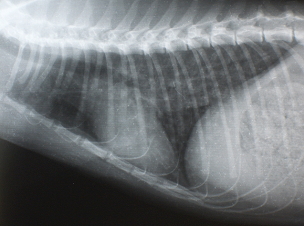

Figure1 3歳半のアメリカンショートヘアー

X線検査

気管支パターンが認められます。また横隔膜が斜めになり、暗い肺野の部分が多くなります。時に右の中葉や左の後葉に硬化像が認められます。